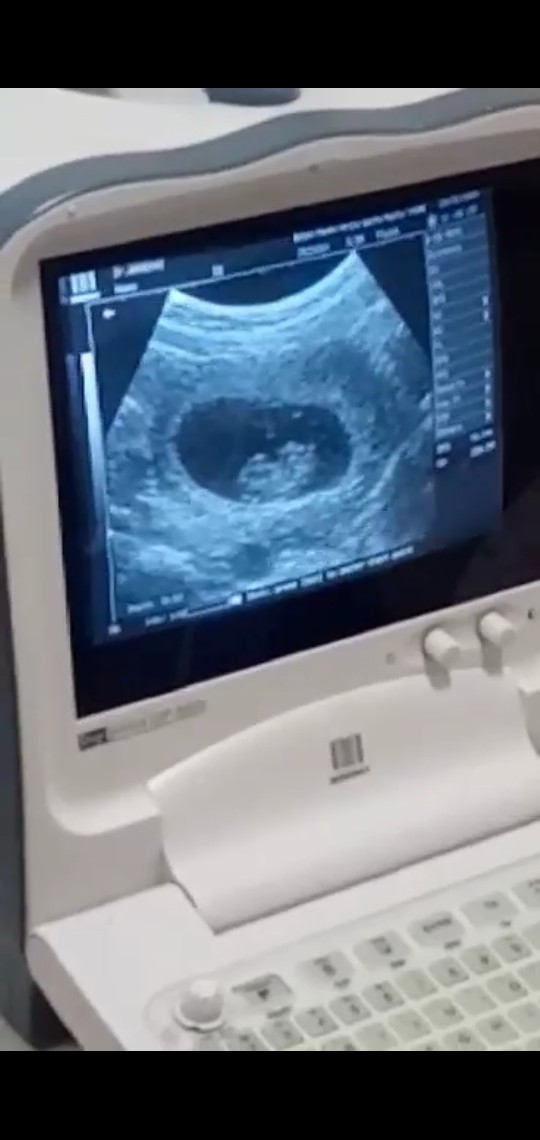

นี้ตอน8w2d ค่าา ได้ยินเสียงหัวใจน้องแล้ว ❤️